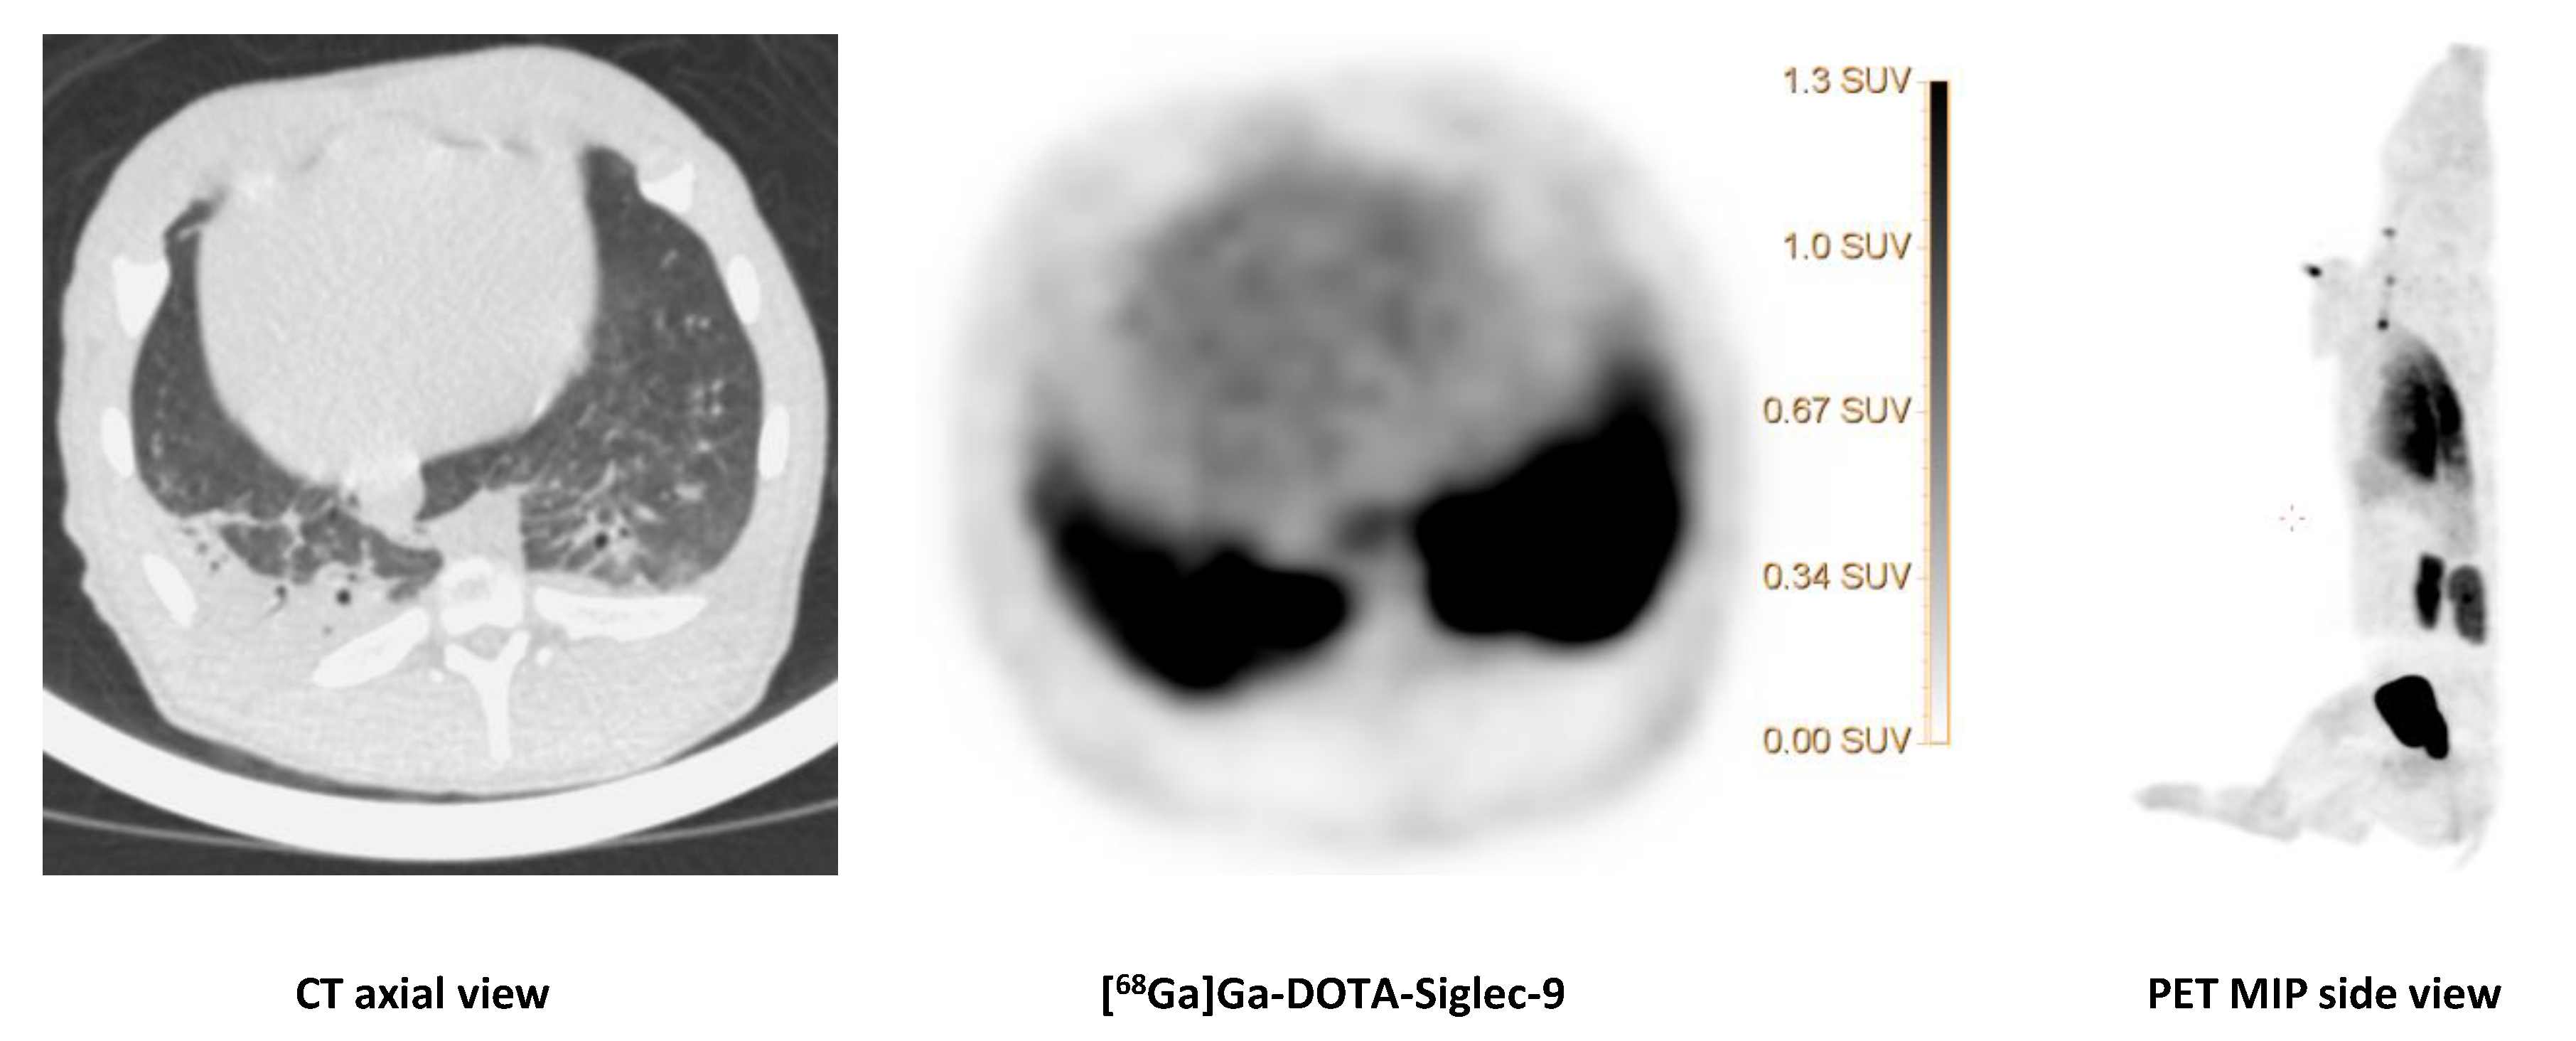

2.5. [68Ga]Ga-DOTA-Siglec-9

We saw no tracer activity neither in the early nor the late images of [68Ga]Ga-DOTA-Siglec-9 in 19 osteomyelitis lesions (Figure 6). Instead, the tracer accumulated in dorsocaudal parts of both lungs of, for example, pig 1 (Figure 7). The CT image showed signs of infectious foci in dorsocaudal parts of both lungs. We noticed, however, a general tendency of [68Ga]Ga-DOTA-Siglec-9 accumulation in the dorsocaudal parts of the lungs. We also observed this in pigs that did not develop OM or pulmonary infections (data not shown). Figure 8 demonstrates in images acquired 10 to 30 min after tracer injection, a marked 68Ga]Ga-DOTA-Siglec-9 uptake in the margin of an inguinal abscess adjacent to the S. aureus inoculation site. In the static images acquired after 60 min, the activity of [68Ga]Ga-DOTA-Siglec-9 decreased. Whereas the activity of [18F]FDG increased slightly in the margin of the abscess (Figure 8).

The CT image (axial view) of the dorsocaudal parts of the lungs of pig 1 showed signs of infection and partial atelectasis (arrow) and the corresponding [68Ga]Ga-DOTA-Siglec-9 uptake in the corresponding anatomical area. Axial views of CT and PET and a MIP (side view) of [68Ga]Ga-DOTA-Siglec-9 distribution in the pig’s body. The SUV scale bar is shown in the axial PET image.